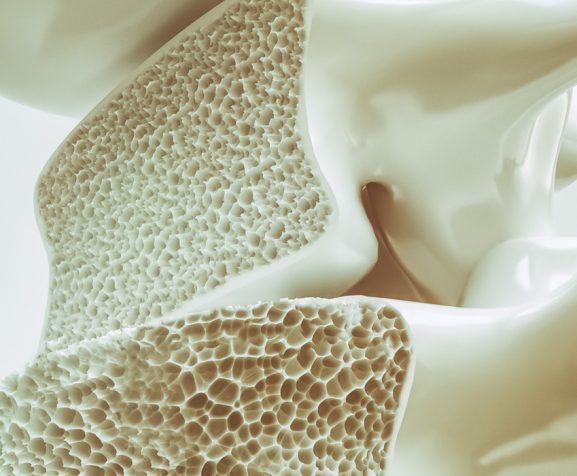

Osteoporosis